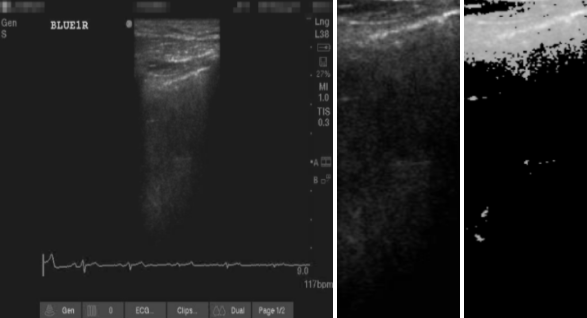

This preprocessing emphasized the key ultrasound patterns used for differential diagnosis while minimizing irrelevant artifacts such as motion blur and rib shadowing. The approach is consistent with elasticity-informed ROI extraction, ensuring the anatomical and physical integrity of the acoustic signal [18, 19]. An example ROI extraction pipeline is shown in Figures 1 and 2.

Refer to caption

Figure 1: Region of interest (ROI) extraction pipeline. (Left) Original LUS frame; (Middle) intensity thresholding to suppress background; (Right) pleural-line-centered crop retaining B-lines and pleural artifacts. This standardized ROI ensures focus on diagnostically relevant structures across patients.

Figure 2: Height Reduction to 50% and final ROI.